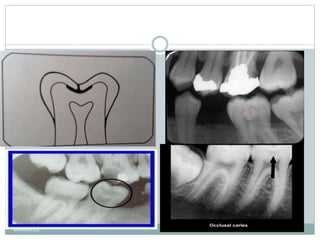

‫داخ‬ ‫به‬ ‫یافته‬ ‫گسترش‬ ‫الی‬‫ز‬‫اکلو‬‫های‬ ‫پوسیدگی‬ ‫کالسیک‬ ‫افیک‬‫ر‬‫گ‬ ‫ادیو‬‫ر‬‫نمای‬‫یک‬ ‫عاج‬‫ل‬

‫یک‬ ‫یر‬‫ز‬ ‫اغلب‬ ‫پهن‬ ‫قاعده‬ ‫با‬ ‫ادیولوسنت‬‫ر‬ ‫ناحیه‬

‫شود‬ ‫می‬‫دیده‬ ‫مینا‬‫در‬ ‫ی‬‫تغییر‬ ‫هیچ‬ ‫یا‬ ‫کم‬ ‫تغییر‬ ‫با‬ ‫شیار‬.

‫دهد‬ ‫می‬ ‫رخ‬‫دندان‬ ‫مینایی‬‫های‬ ‫وشیار‬ ‫پیت‬ ‫در‬ ‫اغلب‬ ‫ضایعات‬ ‫این‬.‫گرد‬ ‫معموال‬ ‫ضایعات‬ ‫این‬

‫شوند‬ ‫می‬ ‫شکل‬ ‫هاللی‬ ‫یا‬ ‫ی‬ ‫بیض‬ ‫شدن‬ ‫گ‬‫ر‬‫بز‬ ‫با‬‫و‬ ‫هستند‬.‫ب‬ ‫های‬ ‫پوسیدگی‬ ‫بین‬‫اق‬‫ر‬‫افت‬‫اکال‬

‫است‬ ‫مشکل‬ ‫افی‬‫ر‬‫ادیوگ‬‫ر‬‫ی‬‫و‬‫ر‬‫از‬ ‫لینگوال‬ ‫و‬

‫ادیولوسنت‬‫ر‬‫نمای‬ ‫اف‬‫ر‬‫اط‬ ‫ا‬‫ر‬ ‫مینا‬ ‫از‬ ‫یکنواخت‬ ‫پوسیدگی‬‫ن‬‫بدو‬ ‫ناحیه‬ ‫یک‬ ‫باید‬‫دندانپزشک‬

‫کند‬‫وجو‬ ‫جست‬.‫غیر‬ ‫مینایی‬‫های‬ ‫میله‬‫بیانگر‬ ‫مشخص‬‫حدود‬ ‫با‬ ‫گرد‬ ‫منطقه‬ ‫این‬

‫کنند‬‫می‬‫احاطه‬ ‫ا‬‫ر‬‫پاالتال‬ ‫یا‬ ‫باکال‬ ‫ضایعه‬ ‫که‬ ‫باشد‬ ‫می‬ ‫ی‬‫مواز‬ ‫پوسیده‬.‫ضایعات‬ ‫اما‬

‫و‬ ‫باکال‬ ‫های‬ ‫پوسیدگی‬ ‫به‬ ‫نسبت‬ ‫مشخص‬ ‫نا‬‫حدود‬ ‫با‬ ‫تر‬‫گسترده‬‫معموال‬ ‫الی‬‫ز‬‫اکلو‬

‫هستند‬ ‫لینگوال‬.‫است‬‫ی‬‫ر‬‫و‬‫ضر‬ ‫کلینیکی‬ ‫یابی‬‫ز‬‫ار‬.